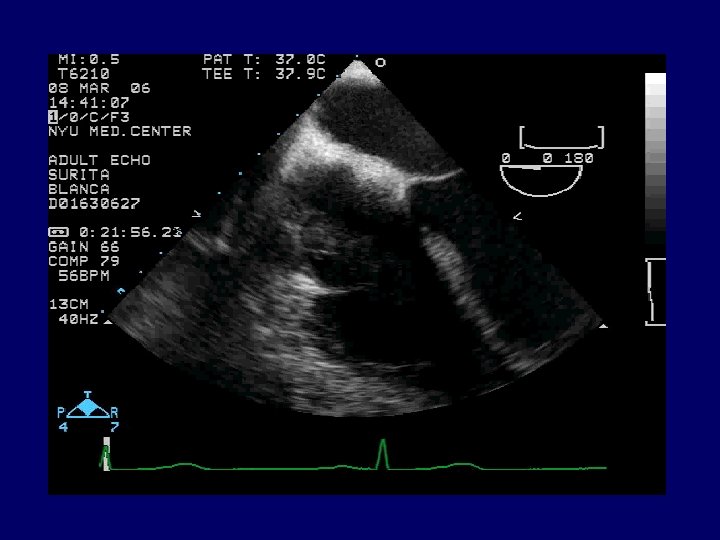

Radiology CXR: mild interstitial edema and cardiomegaly. Transthoracic echocardiogram (TTE): large 6. 5 x 2. 0 cm pedunculated mass attached to the lateral free wall of the right atrium separate from the tricuspid valve leaflets, with prolapse of the mass across the tricuspid valve and associated severe tricuspid insufficiency. A diagnostic procedure was performed…

Echocardiography

TRICUSPID INDENTATION ATRIAL CUFF

Final Diagnosis: Subacute bacterial endocarditis Giant endocardial vegetation due to Vancomycin Resistant Enterococcus faecium